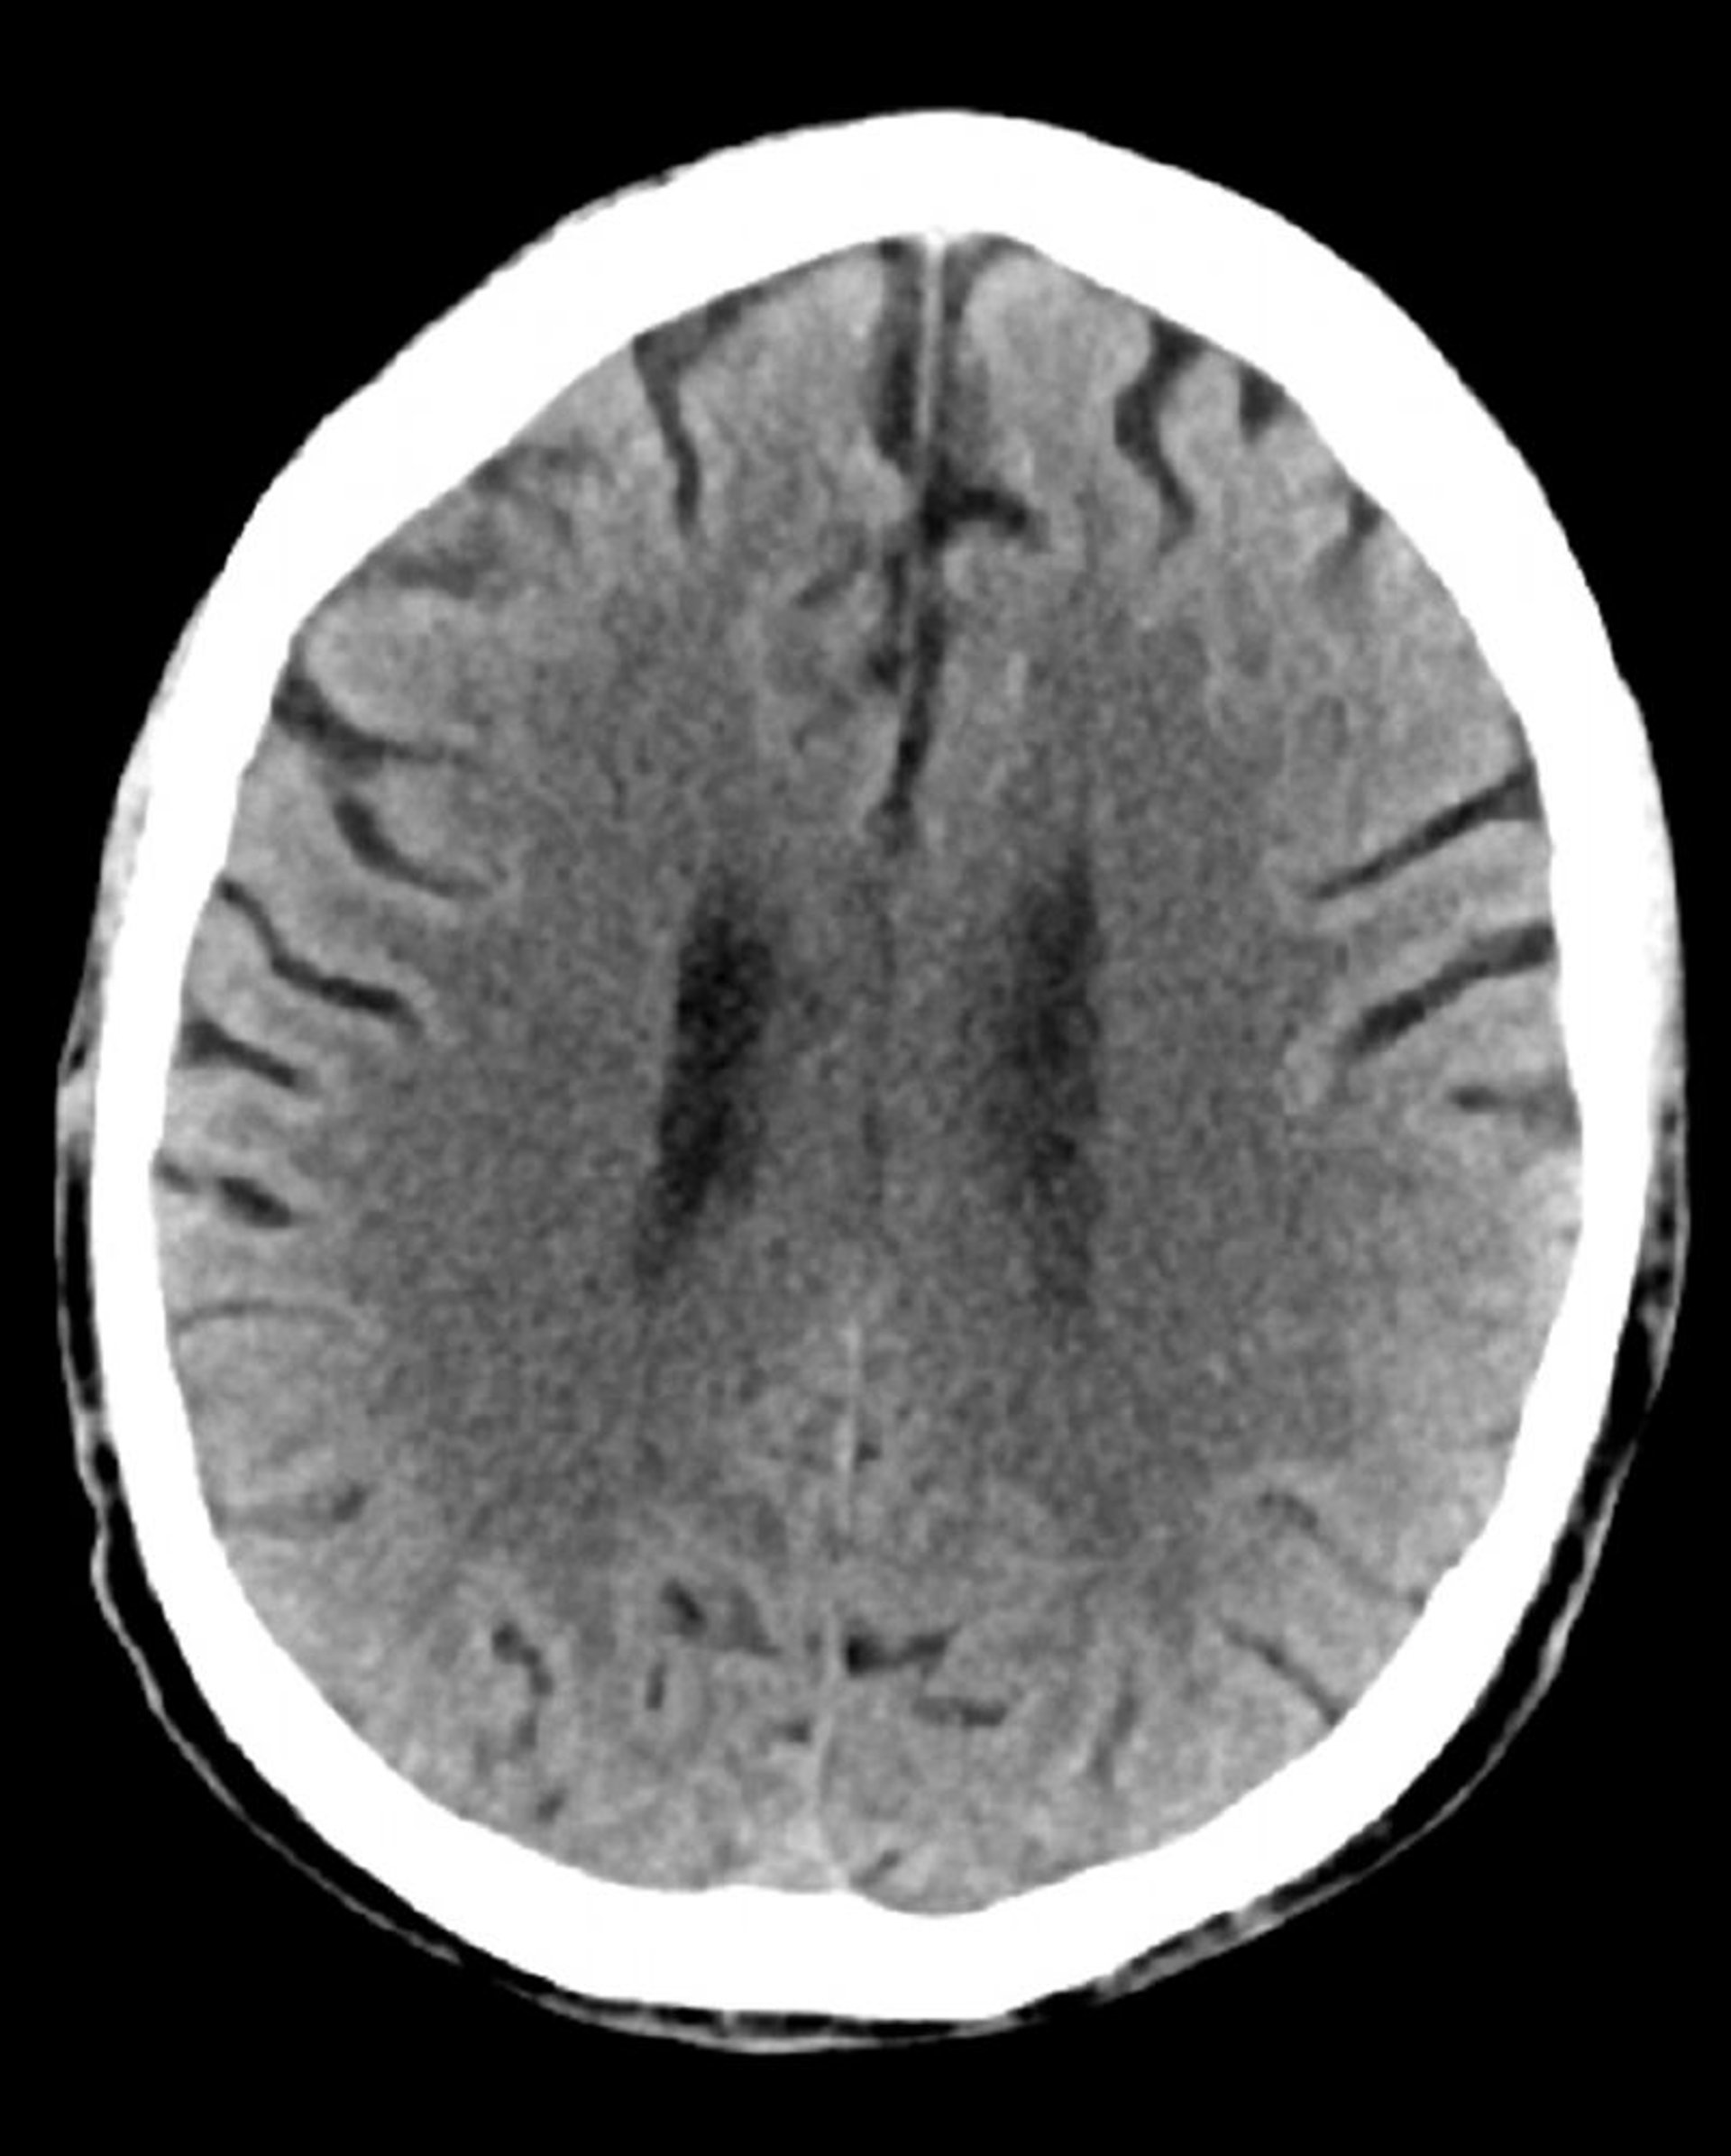

Tomodensitométrie normale de la tête (adulte, 74 ans) – Diapositive 3

Cette image est une TDM normale de la tête d'un adulte âgé de 74 ans. Par rapport à la TDM normale de la tête d'un patient de 30 ans, les ventricules et les sillons sont plus grands. Ces signes sont normaux dans ce groupe d'âge.